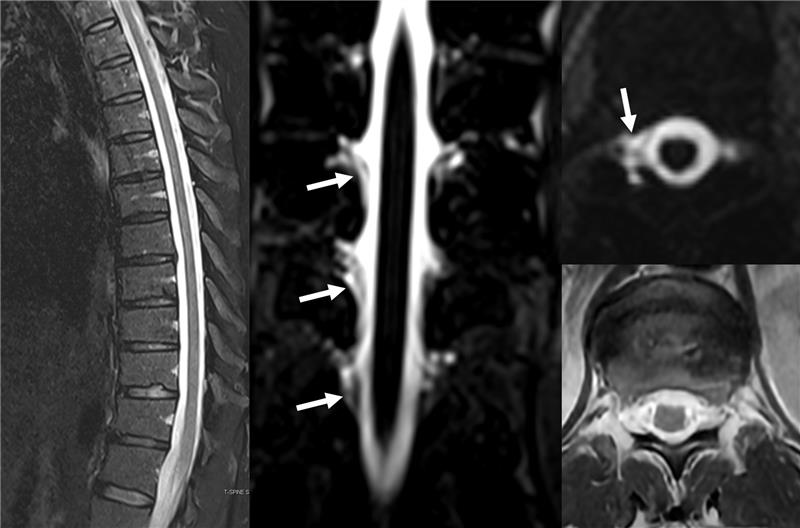

This leak or several has the audacity to not leak during a myelogram I traveled for days for but leaking multiple times daily is not a problem at all. Neither are positional attacks going from 0-10 in 3 minutes. I hate #spinalCSFleak as well as my life. 😭